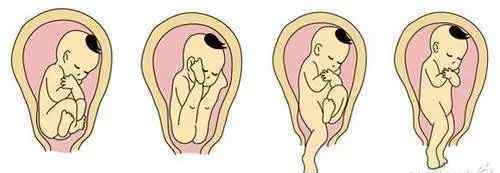

正常胎位只有一个,就是枕位(头位的一种),即胎儿宝面向前(靠近母亲腹部),胸部面向后(靠近母亲脊柱),双手交叉放在胸前,双腿弯曲,头部弯曲,枕部(头顶)最低。

除了这种胎位,就算是头位,也算胎位不正。

头位是指胎儿低着头,臀部朝上的姿势。头位分为枕后位、枕后位、额位和面部位。

上图为4种头位情况,但只有图1显示正常胎位,图2、3、4均属于胎位异常。